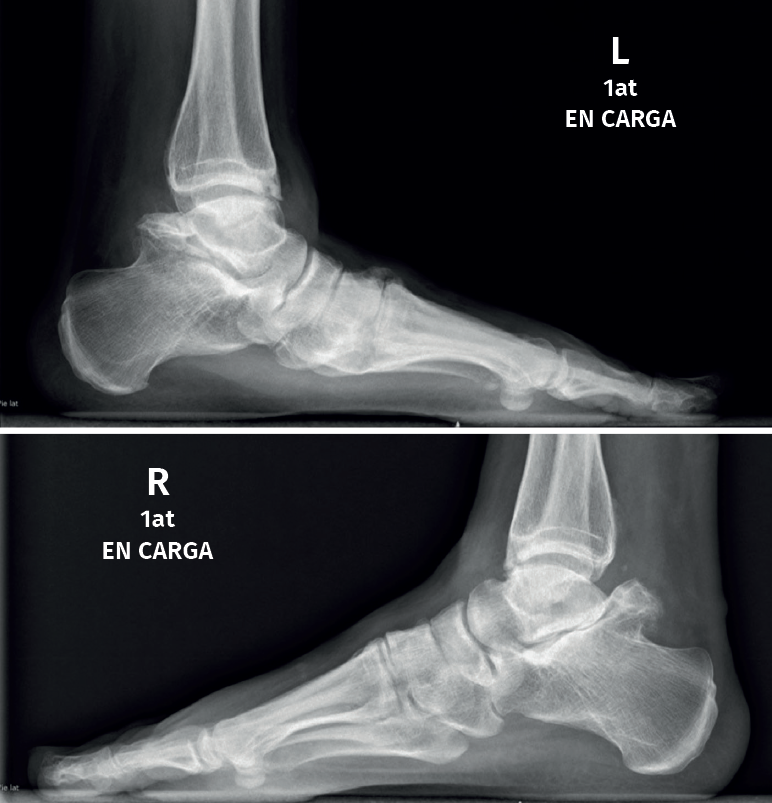

Es una entidad rara de etiología desconocida que afectaría a 1 de cada millón de personas, es 3 veces más frecuente en el varón y presenta el aspecto clínico e histológico de un osteocondroma que asienta en la epífisis en vez de la zona metafisaria del hueso en crecimiento(24,25)(Figuras 4 y 5).

Radiológicamente, se caracteriza clásicamente por(23):

- Crecimiento óseo no uniforme.

- Centros de osificación desconectados de la epífisis.

El síndrome de Trevor o displasia epifisaria hemimélica es acaso la forma más característica de alteración del desarrollo del astrágalo. Toda la bibliografía coincide en su rareza, al describir casos aislados casi siempre en edad infantil(44,45) y algunos con afectación generalizada de las epífisis de una mitad del cuerpo(46,47), cifran en 150 los casos comunicados hasta 2018 y se replantean este dato por la confusión diagnóstica que puede darse, ya que, en el caso del astrágalo, la apariencia radiológica puede ser muy variable(48) o incluso cuestionable al ser bilateral, como el caso de una mujer adulta de 42 años con pie plano doloroso publicado por Dávila y Llanos en nuestra revista(49).

En adultos (Figuras 6 y 7), se cita como causa de pinzamiento doloroso en la cámara posterior del tobillo(50), aunque también como causa de impingement anterior(51), o confundirse con un osteocondroma a pesar de sus diferencias histológicas. Mientras el osteocondroma reproduce una arquitectura similar a la de la placa de crecimiento, la displasia epifisaria hemimélica muestra en su cubierta cartilaginosa áreas con acúmulos de condrocitos y pequeñas áreas de cartílago calcificado no reabsorbido(52). Por otra parte, la presencia de osteocondromas en la parte posterior del astrágalo es muy rara. En una serie de 7 casos en los que se produjo rotura a través del pedículo en relación con ejercicio físico, Carpintero et al. no señalan ninguna en esta localización(53).